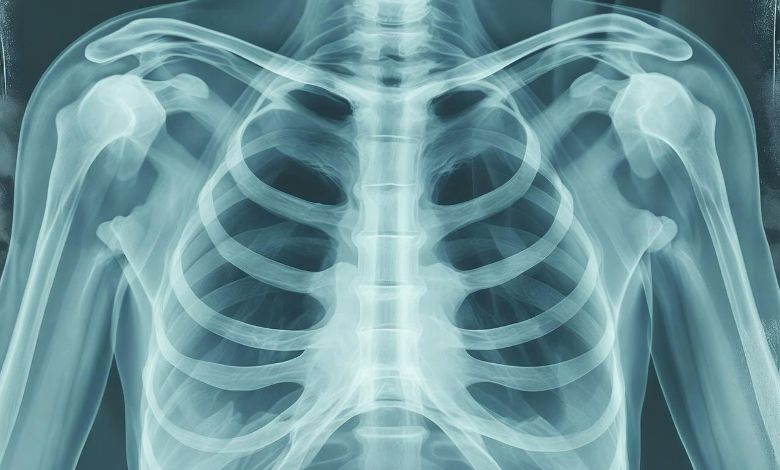

A CT scan( Computed Tomography scan) is a medical imaging test who uses X- rays and computer processing to create detailed cross- sectional images of your body.

Result of ct scan how long